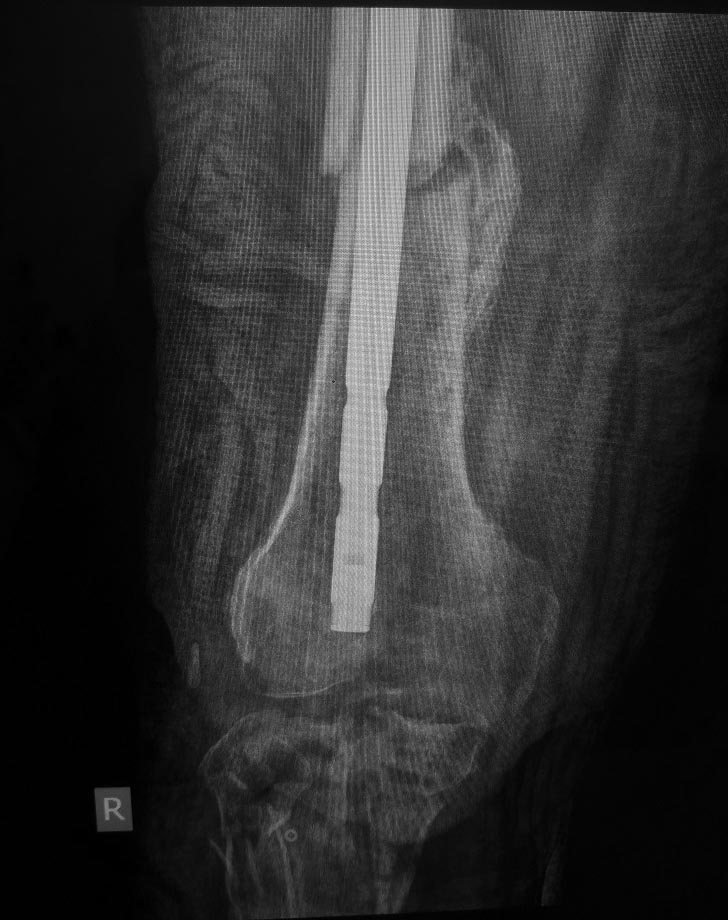

Вот такой случай. У пациента хронический остеомиелит проксимального

отдела голени. Ложный сустав с/3-н/3 бедренной кости. Был

спице-стержневой АВФ бедро-голень. Прям на штифте.

1. Резекция проксимального отдела голени 8 см приблизительно,

собственной связки надколенника, самого надколенника?. Промывание;

2. Удаление штифта;

3. наложение АВФ спице-стрежневого на бедро и голень.

Может еще есть какие мысли. Еще есть мысль со спейсером,

но не знаю????